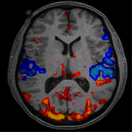

Over the years brain neuro-imaging techniques have become more refined and are being used at major institutions such as UCLA and Harvard. Brain neuro-imaging techniques fall into three major categories:

MRI is a neuroimaging technique that is designed to look at physical/anatomical structures of the brain. It has a temporal resolution of 2 seconds-which means it is too slow to measure neuro function. Neuro function is a measure of how the brain thinks and the speed at which it processes information, which is in milliseconds.

fMRI is similar to MRI, but measures anatomical brain engagement. In other words: How well does one anatomical brain system work with another brain system? However, although it has a faster resolution, it is also too slow to measure the detailed information processing function of the brain.

CT Scan is a neuro-imaging technique and similar to MRI, but with even less resolution than MRI, which means it is too slow to measure neuro function.

PET and SPECT techniques measure metabolic activity within areas of the brain. These are gross measures, which means they are not detailed or specific measurements and cannot show neuro function.

QEEG and EEG techniques are fast enough to measure neuro function down to 100th of a millisecond, which more closely approximates brain processing speed. These faster recordings allow clearer functional measurements of brain performance with regard to thinking and processing information.

The conventional approach to brain measurements focuses on the anatomy of brain structures only, such as MRI or CAT Scans. These techniques are done to rule out basic damage to the brain structure due to severe head injuries or seizure damage. These tools and their results are not intended to be an effective measurement for mild head injuries, much less identifying neurodevelopment. These tools are too slow to measure neuro function. These methods yield great results when attempting to rule out lesions or damage to different parts of the brain’s structure. However, these tests yield little to no information concerning how well the brain is performing, especially under task or pressure.

Three other useful and popular techniques utilize fMRI, PET, or SPECT scans, which highlights anatomical, structural, or metabolic issues. fMRI is similar to MRI, but measures anatomical brain engagement. How well does one anatomical brain system work with another brain system? It has a faster resolution than MRI or CAT scan, but is still too slow to measure the detailed information processing function of the brain. PET and SPECTtechniques measure metabolic activity within areas of the brain. They are not detailed and cannot show neuro function. None of the method mentioned is fast enough to read the changes that occur in the speed of processing of the brain.

Presently, the only technique fast enough to help measure true brain processing issues is the EEG/QEEG. This method measures brain waves at the scalp’s surface. QEEG and EEGtechniques are fast enough to measure neuro function down to 100th of a millisecond, which more closely approximates brain processing speed. These faster recordings allow clearer functional measurements of brain performance with regard to thinking and processing information.